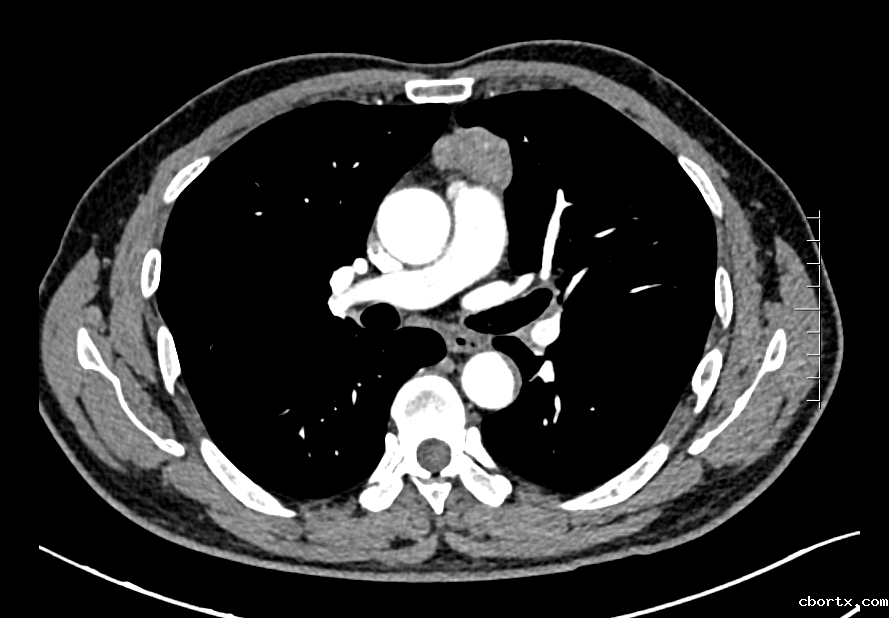

该名患者因肌无力症状在体检时发现前纵隔占位,CT提示前纵隔结节影,长径约4cm,考虑胸腺瘤。胸外科结合患者病情、既往史,并与患者及家属充分沟通后,决定为患者行“经皮天平拉钩剑突下单孔VATS前纵隔占位切除术”。